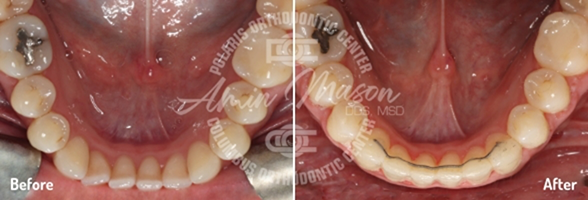

Case 5

This 17-year-old patient came into our office with a multitude of problems we’ve helped many other people fix: teeth crowding, an underbite, and a crossbite of the back teeth (where the upper and lower teeth are offset from left to right). Each of these issues was quite severe, however, and the patient was previously told he needed surgery to correct them all. He said he didn’t want to undergo surgery, so Dr. Mason put together a customized treatment plan. First, he placed a temporary anchorage device (TAD) supported expander to increase the size of the patient's hard palate, and he also used another TAD on the lower teeth to close the spaces. Then, Damon damon self-ligating braces helped move the teeth into their ideal positions. One of the patient’s lower premolars was removed as well. In the end, the patient was able to avoid surgery and achieve excellent results that he could not believe.